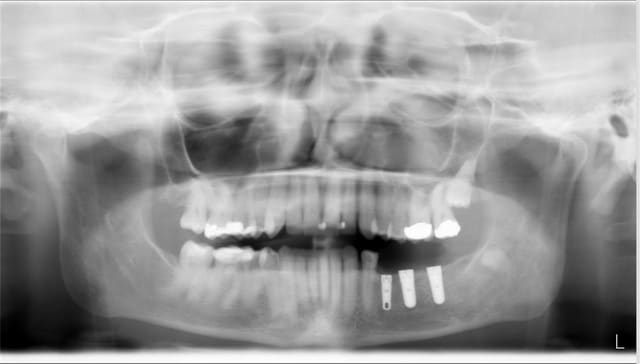

un avis implantaire pour mon premier implant au niveau d'une 36 extr faite en sept 2009

quelle longueur environ? je pensais a un 4/10mm ...

un scanner est il indispensable dans ce cas ?

Ps extr delicate et os tres corticalisé...

derniere radio faite avec angulateur .... et en mars 2010

toutes les données que tu nous montre ne montrent pas un critere important : la largeur de crete c'est quand meme important pour ce secteur.

la crete est tres large et peu de concavite en L.

c'est juste la longeur qui m'inquiete

le cone apres extr dans l'alveole mesure 19 mm et avec la radio je mesure 18 mm : il y a peu de deformation